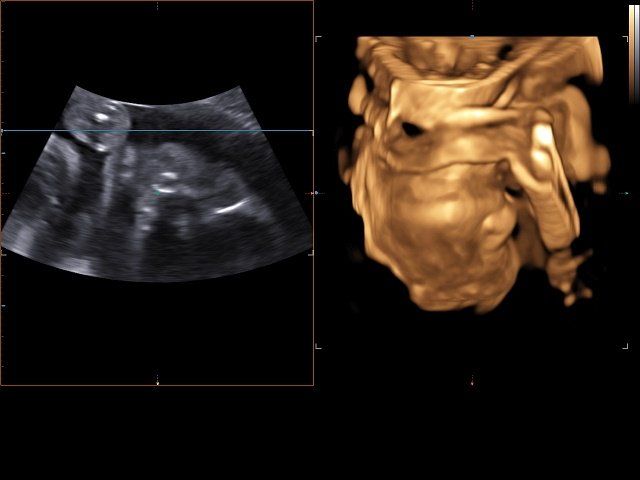

Ecografia 3D/4D

L'ecografia 3D consente di ottenere delle immagini statiche, non in movimento, ma in pratica delle foto delle fattezze del feto.

Dottore di ricerca Università di Palermo in Ecografia 3D/4D

È specializzato nell’eseguire screening del I trimestre ed ecografie in 3D/4D e usa apparecchiature di alto livello a elevata tecnologia. Ha partecipato a numerosi congressi anche in qualità di relatore e pubblicato numerosi articoli scientifici in campo ostetrico e ginecologico.